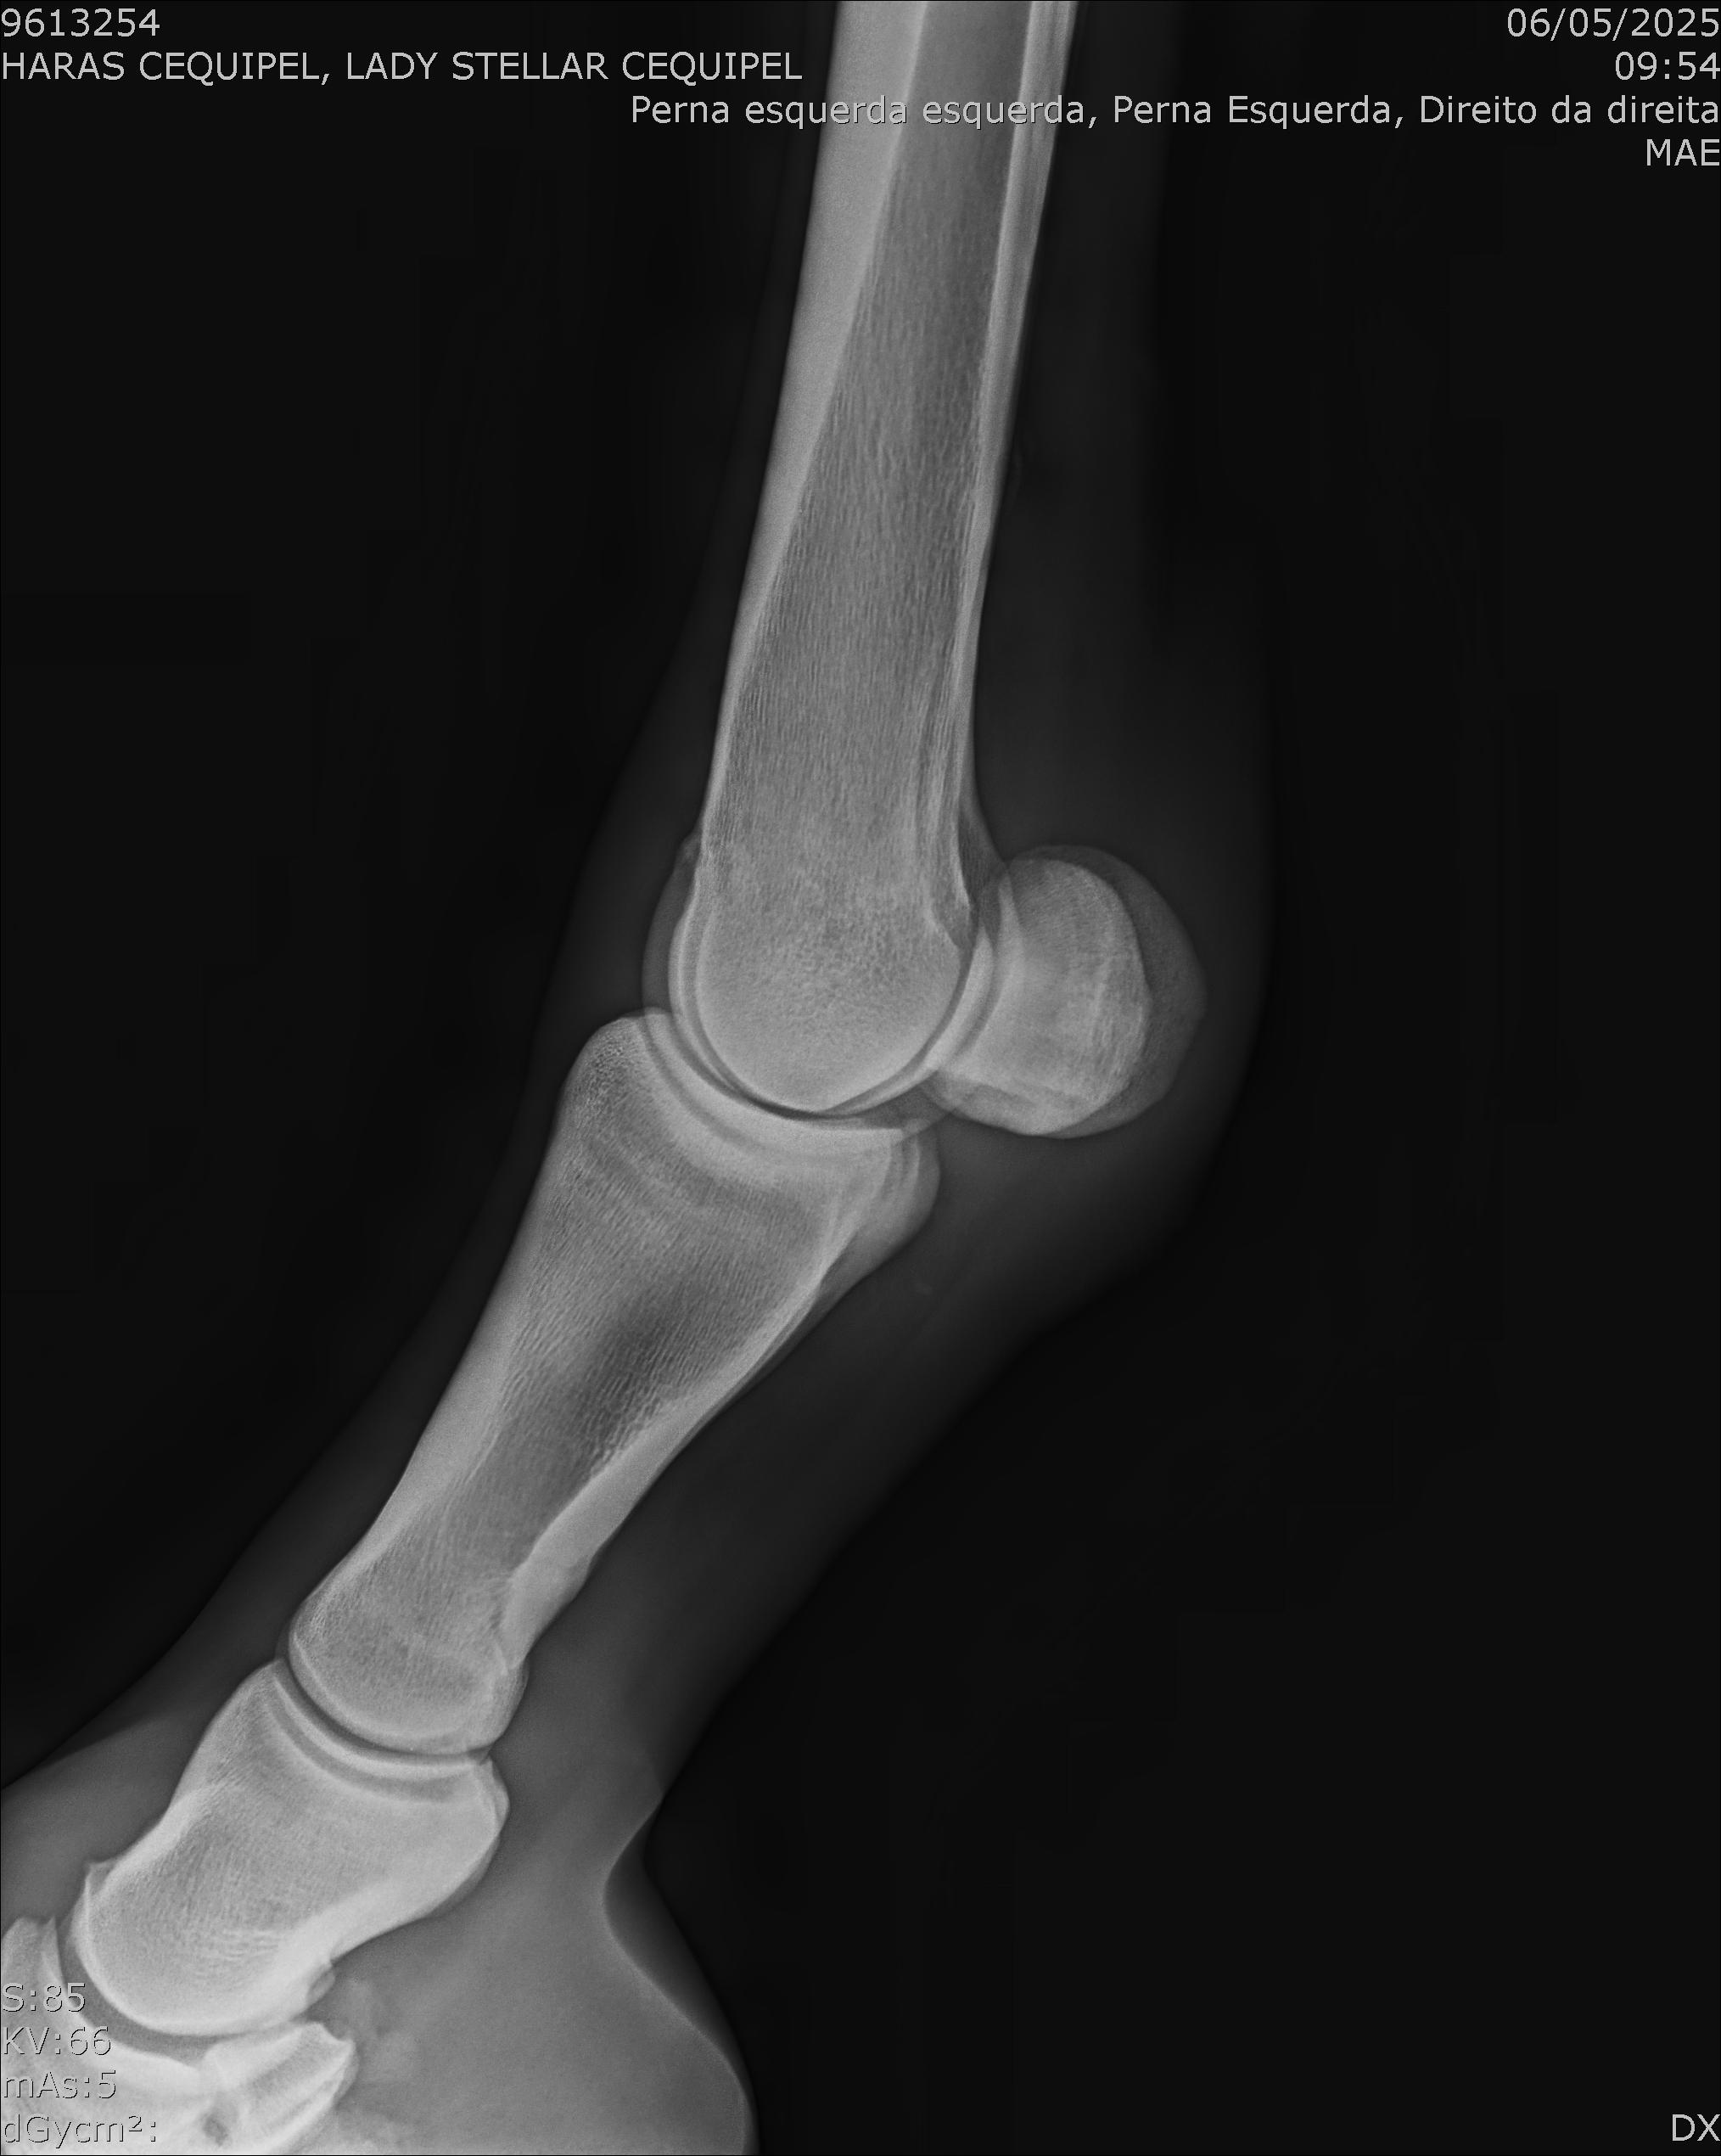

:: RAIOS-X DO LOTE